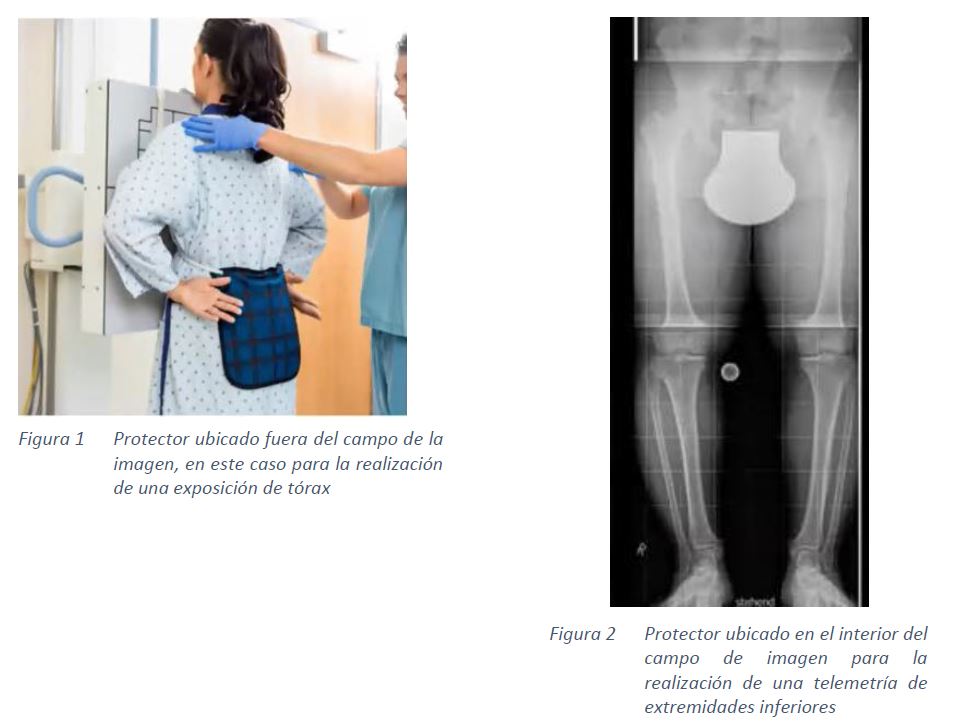

La ubicación de los protectores en los pacientes puede ser:

- Ubicado fuera del campo de imagen

- Ubicado dentro del campo de imagen